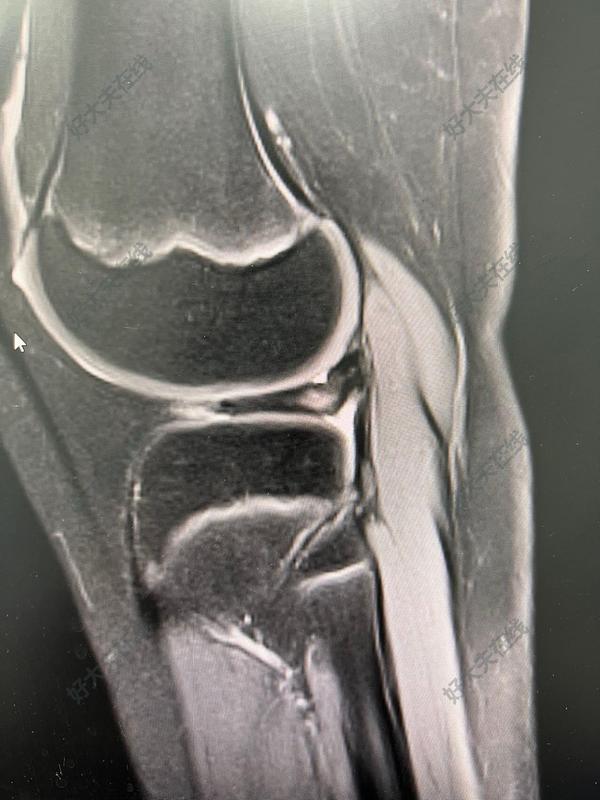

治療前 膝關(guān)節(jié)痛之半月板。 患兒10歲,因膝關(guān)節(jié)痛就診于小兒內(nèi)科,行相關(guān)檢查,發(fā)現(xiàn)半月板問題,磁共振可見膝關(guān)節(jié)外側(cè)盤狀半月板并撕裂,行關(guān)節(jié)鏡盤狀半月板成型術(shù)。 治療后 治療后即刻 此為另一例術(shù)前磁共振,于小兒骨科行關(guān)節(jié)鏡治療,術(shù)后恢復(fù)良好,疼痛減輕。